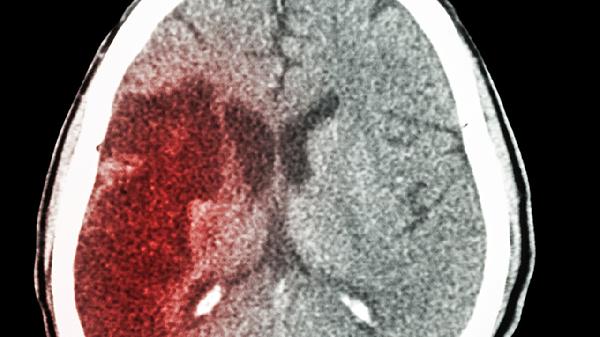

这4件事不注意,不能怪脑肿瘤找上门,4种异常早就应该警惕了

你是不是经常熬夜刷手机,第二天头痛欲裂还觉得是“没睡好”?或者偶尔眼前发黑,却以为是低血糖?别大意!这些看似普通的身体信号,可能是大脑在向你“求.救”。脑肿瘤的早期症状往往被我们忽略,等到发现时已经错过最佳干预时机。今天就来聊聊那些容易被忽视的“危险信号”和日常生活中的“高危行为”。

一、4种异常,可能是大脑在“报.警”